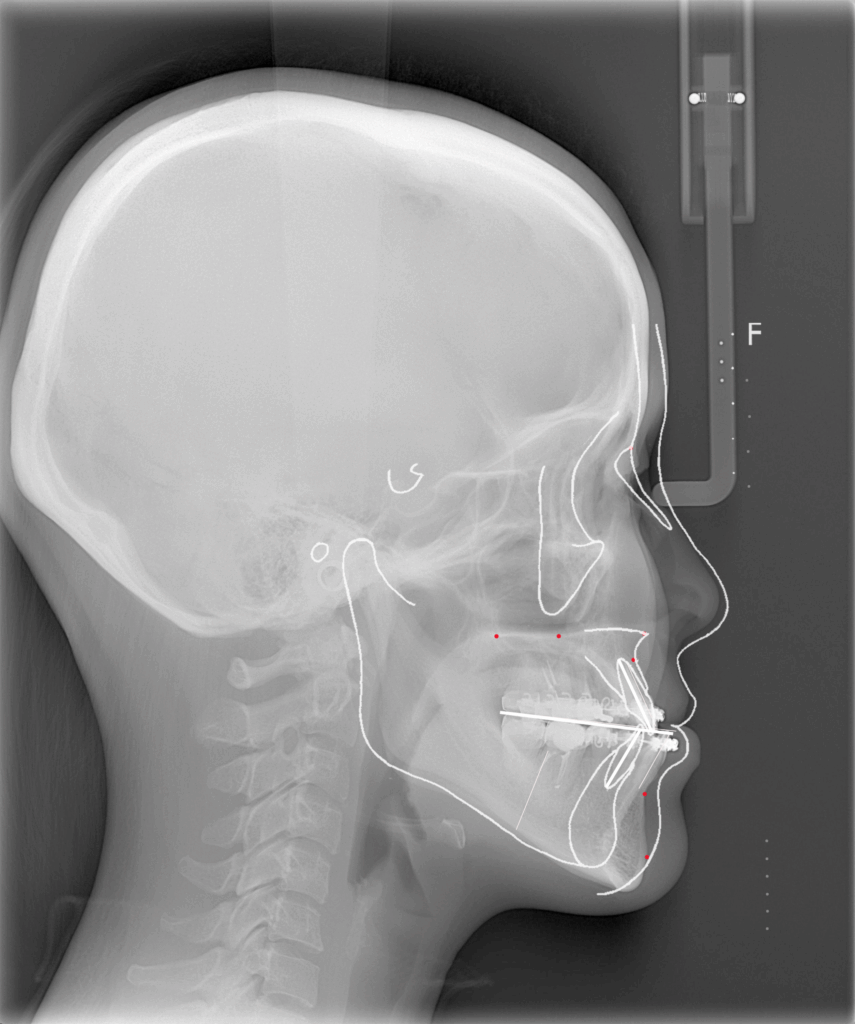

レントゲンを用いて骨格の特徴を把握します。白線の輪郭は標準的な骨格を表しています。標準骨格と比べると、下顎が前に出ていて、なおかつ垂直方向に長いことがわかりました。

下顎はSSROで後方に移動させ、上顎は鼻下の陥没感を改善するために上顎前歯の先端を回転中心として時計回転させて鼻下の骨を前方に出す計画としました。顎先は中抜きオトガイ形成で垂直方向の長さを短縮することにしました。

白線の標準骨格に一致するように骨の移動量を決めていきます。上顎は鼻下で2mm前進し、臼歯部で2mmほど上方に移動させます。全体として上下顎は時計回転することになります。顎先は4mmの中抜き短縮です。